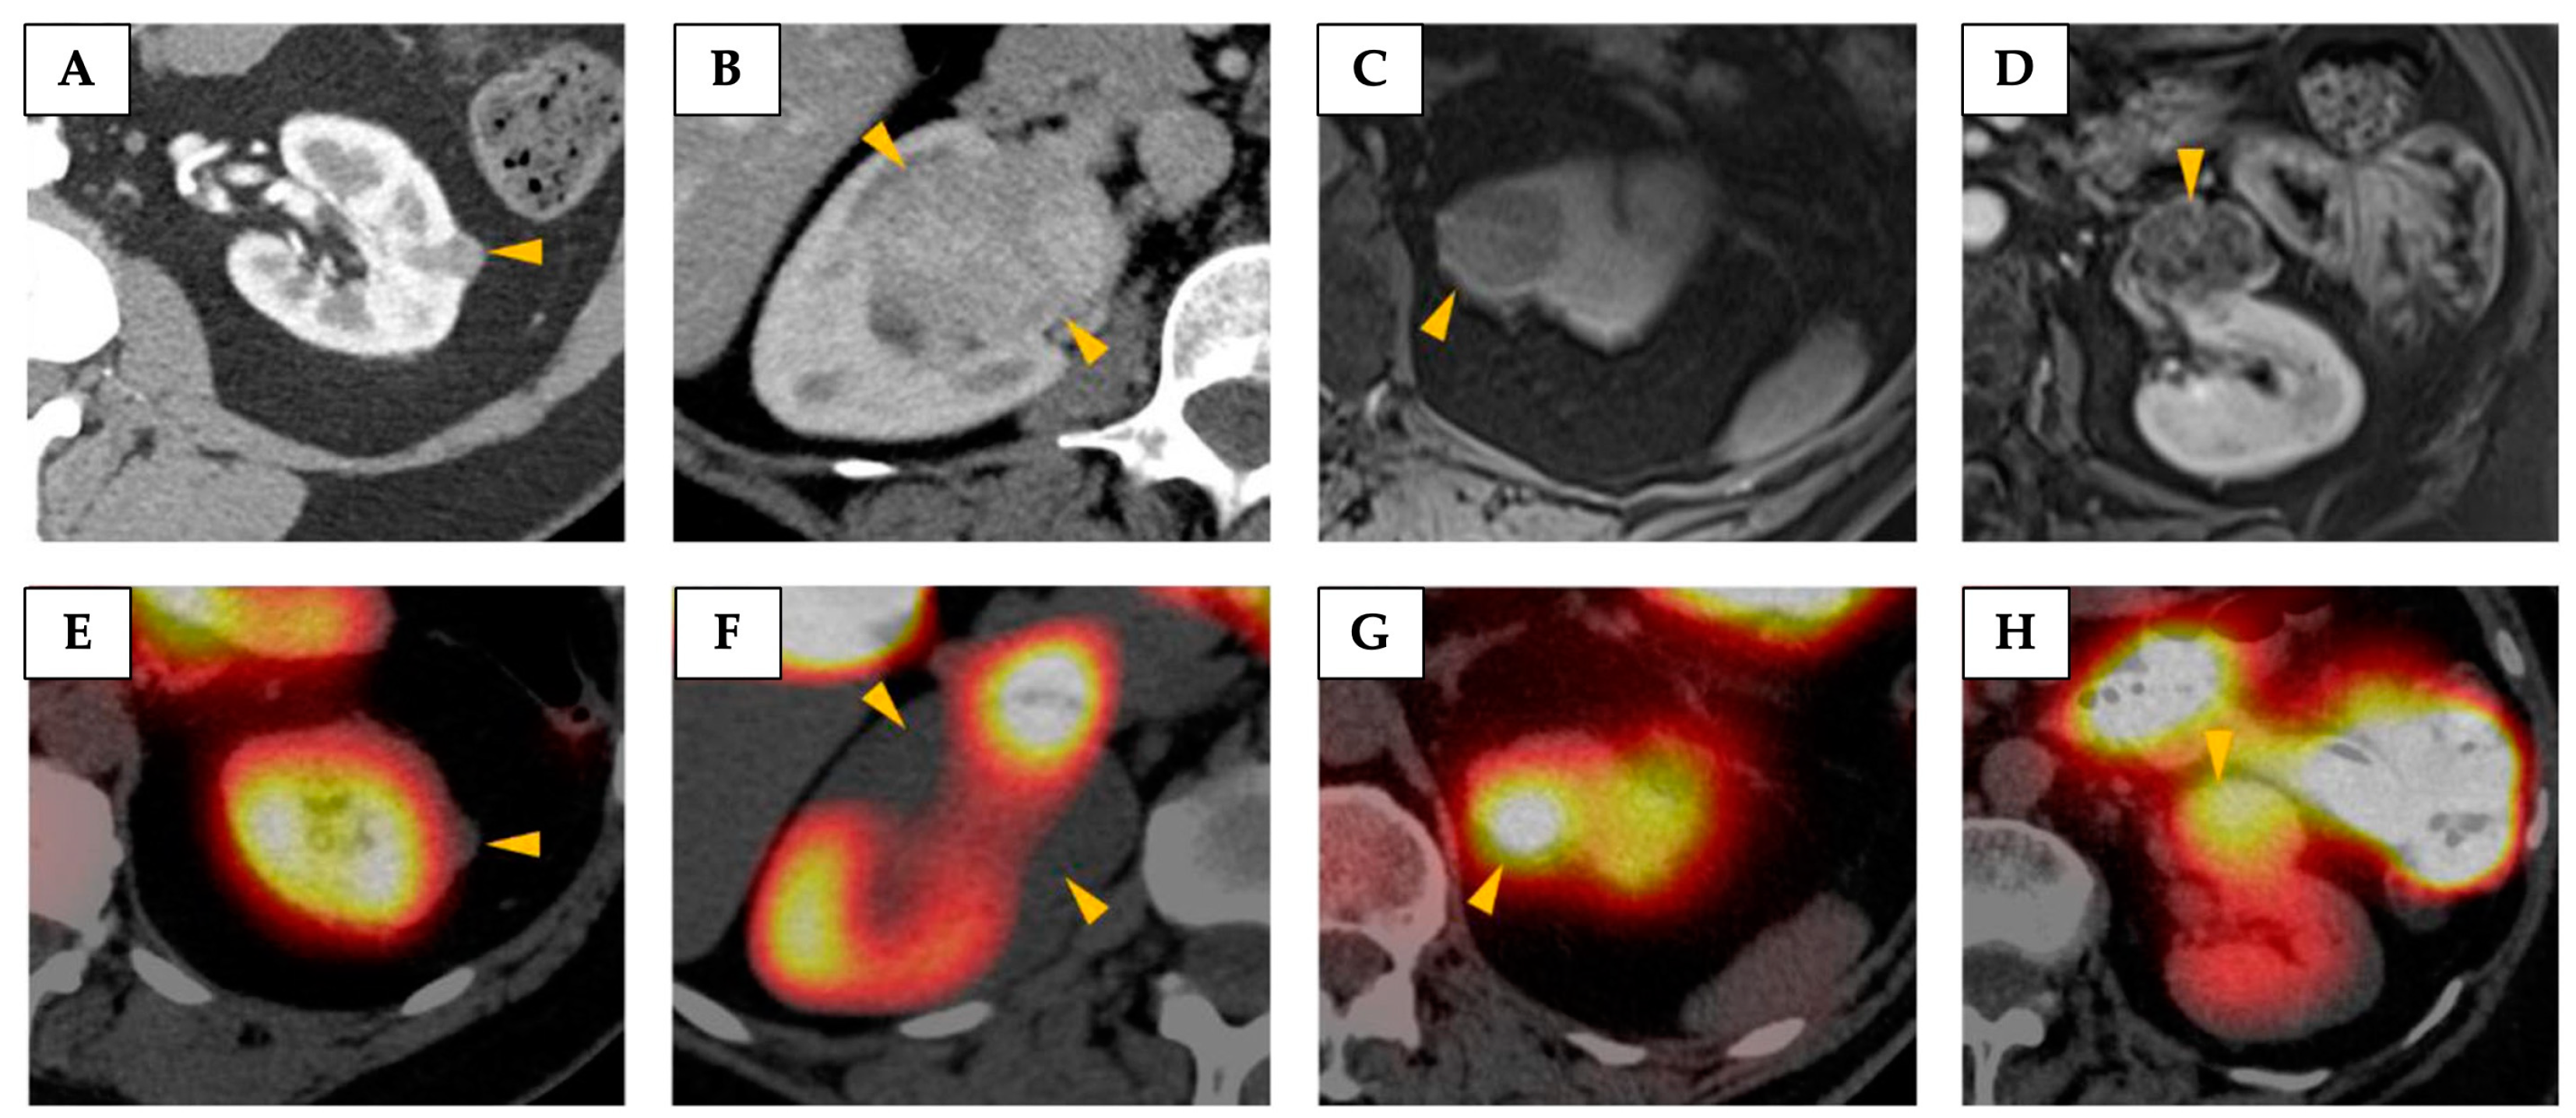

4.1.2. 99Tc-Sestamibi SPECT

- Wilson, M.P.; Katlariwala, P.; Murad, M.H.; Abele, J.; McInnes, M.D.F.; Low, G. Diagnostic Accuracy of 99mTc-Sestamibi SPECT/CT for Detecting Renal Oncocytomas and Other Benign Renal Lesions: A Systematic Review and Meta-Analysis. Abdom. Radiol. 2020, 45, 2532–2541. [Google Scholar] [CrossRef]

- Basile, G.; Fallara, G.; Verri, P.; Uleri, A.; Chiti, A.; Gianolli, L.; Pepe, G.; Tedde, A.; Algaba, F.; Territo, A.; et al. The Role of 99mTc-Sestamibi Single-Photon Emission Computed Tomography/Computed Tomography in the Diagnostic Pathway for Renal Masses: A Systematic Review and Meta-analysis. Eur. Urol. 2024, 85, 63–71. [Google Scholar] [CrossRef]

- Rowe, S.P.; Gorin, M.A.; Solnes, L.B.; Ball, M.W.; Choudhary, A.; Pierorazio, P.M.; Epstein, J.I.; Javadi, M.S.; Allaf, M.E.; Baras, A.S. Correlation of 99mTc-Sestamibi Uptake in Renal Masses with Mitochondrial Content and Multi-Drug Resistance Pump Expression. EJNMMI Res. 2017, 7, 80. [Google Scholar] [CrossRef]